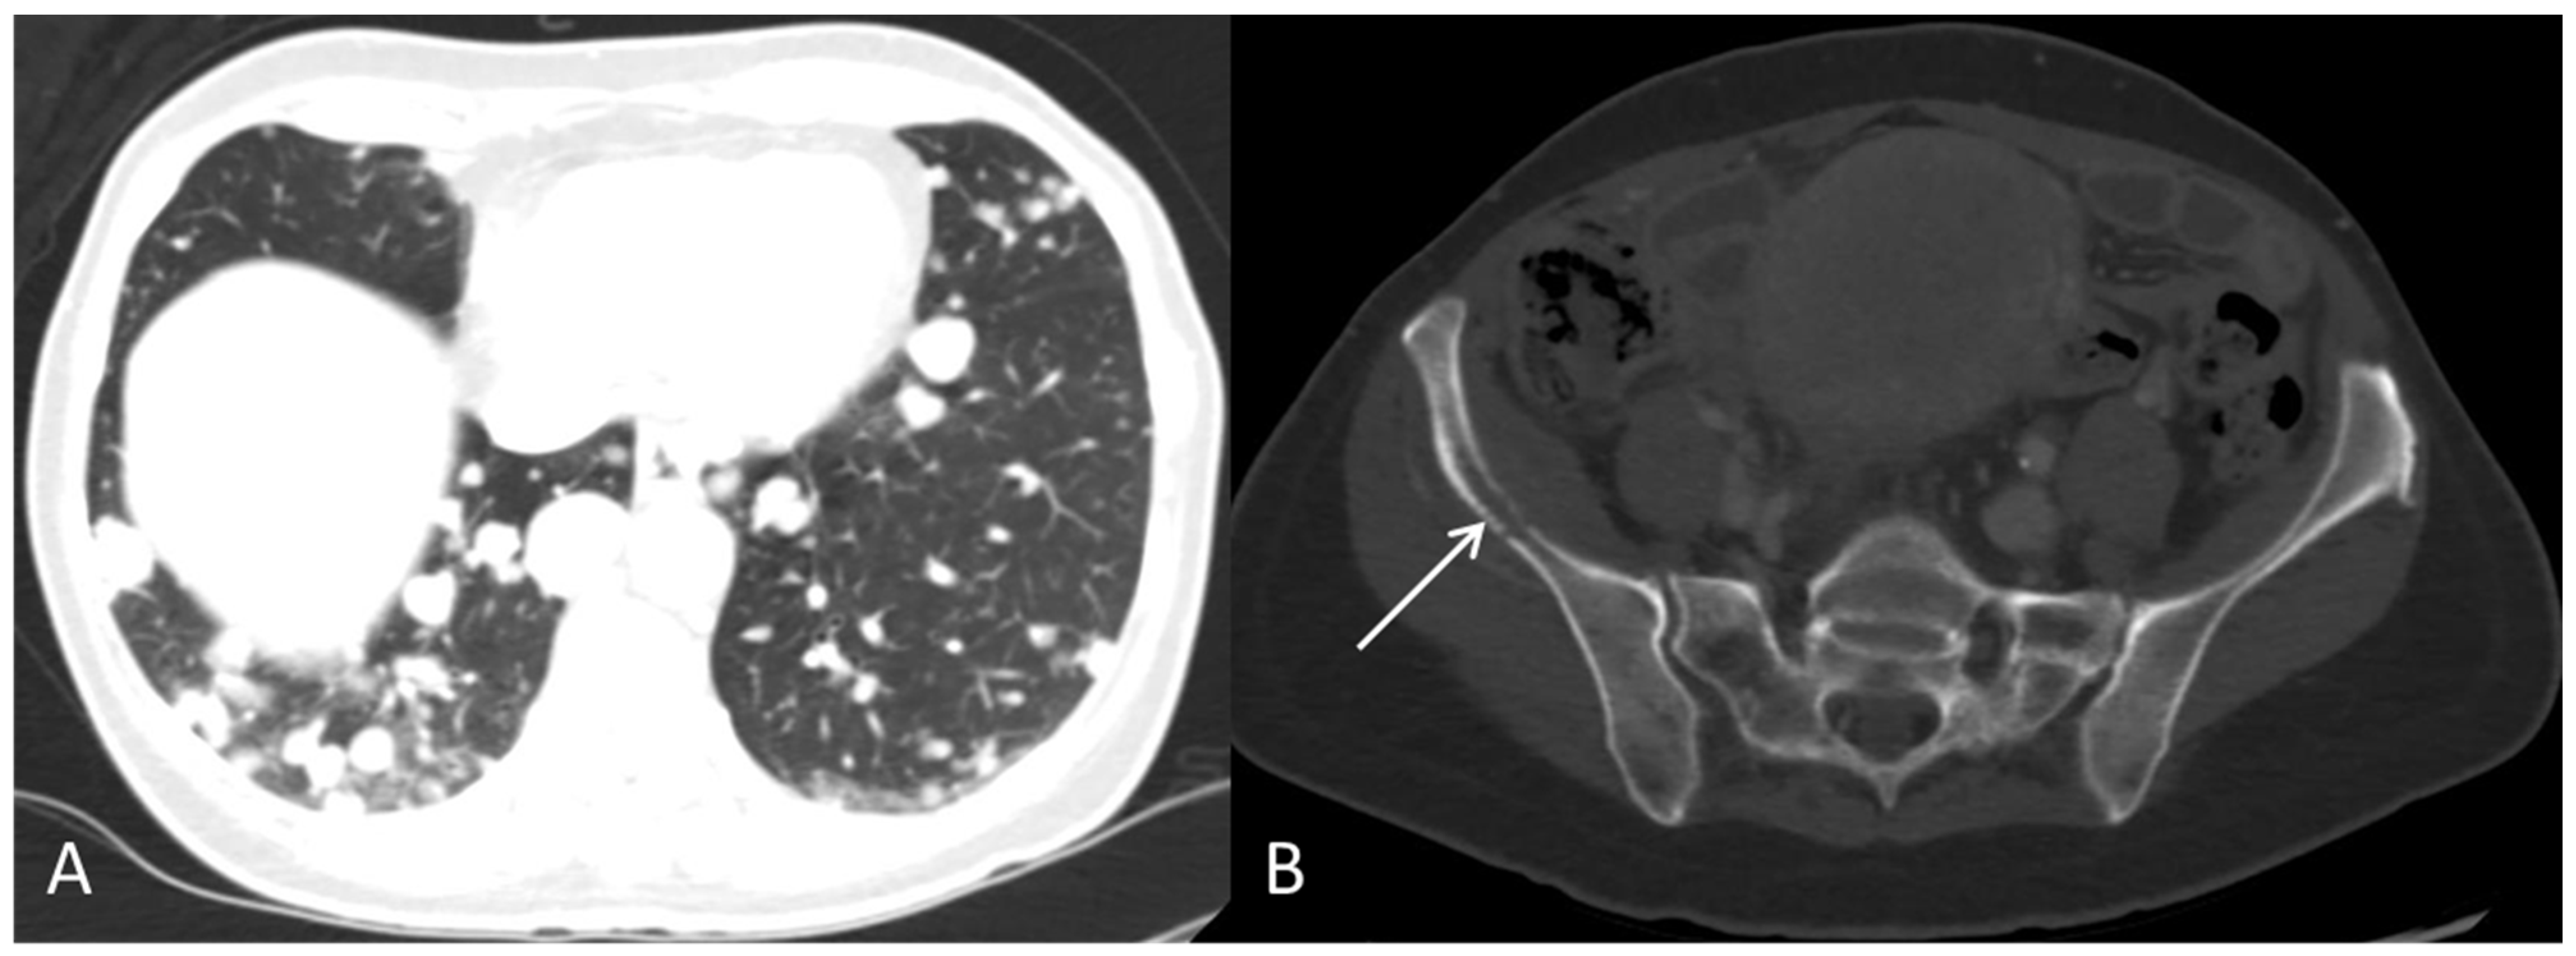

Dejanovic, D.; Boennelycke, M.; Amtoft, A.G.; Christensen, C.B.; Wetterstroem, V.; Loft, A.; Noettrup, T.J. Disseminated Primary Uterine Hepatoid Adenocarcinoma with α-Fetoprotein Production Demonstrated on 18F-FDG PET/CT. Diagnostics 2022, 12, 1447. https://doi.org/10.3390/diagnostics12061447